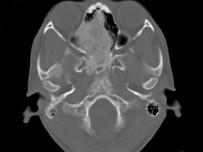

问题 女,17岁,鼻阻塞、头痛两年.如图所示符合筛骨病变最可能的诊断是 ( )

选项 A、骨瘤 B、骨化性纤维瘤 C、纤维异常增殖症 D、软骨瘤 E、成骨肉瘤

答案 B